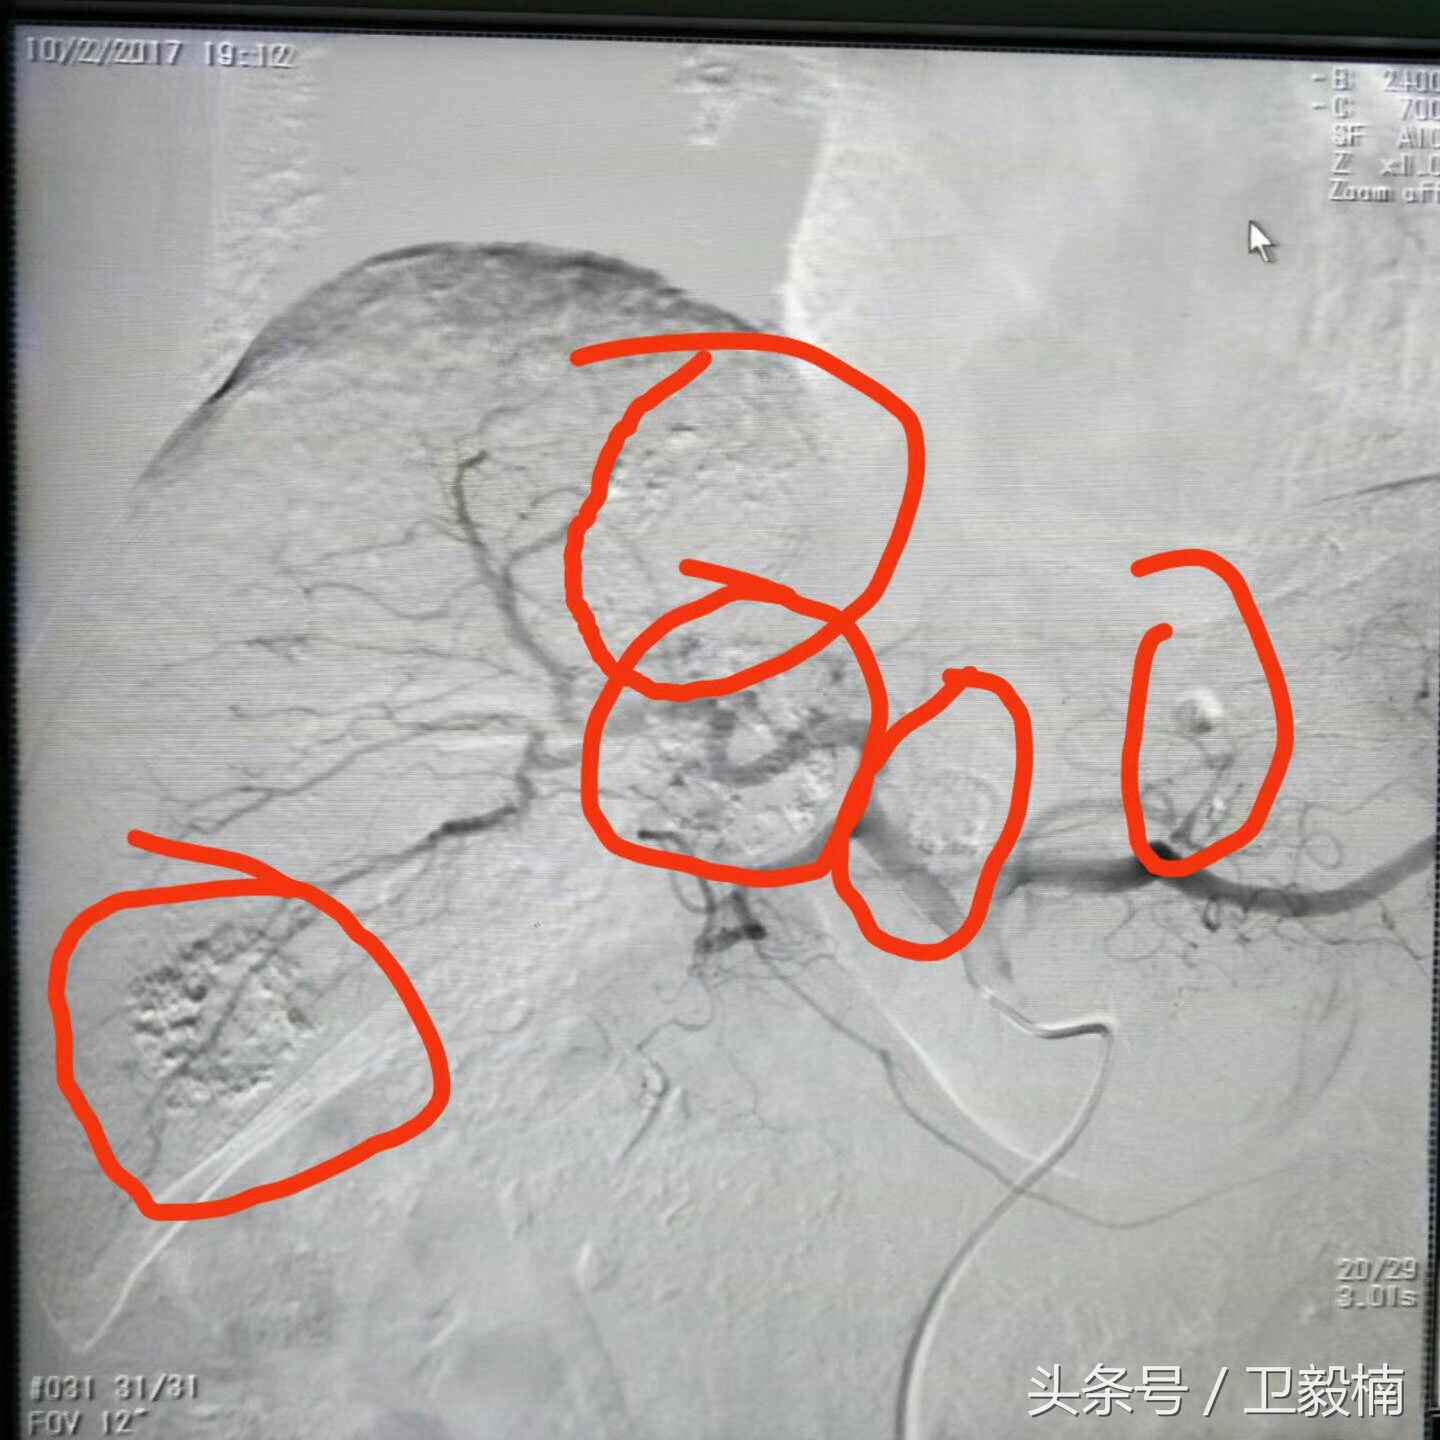

栓塞前

栓塞后可见碘油明显沉积